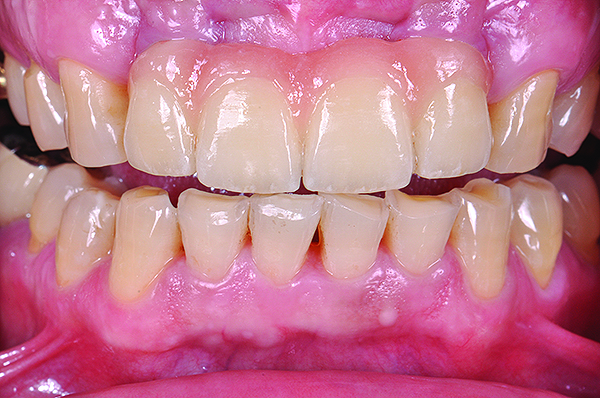

Fig 6. Preoperative view of patient requiring esthetic changes up to at least the bicuspids (Fig 5); postoperative view with CL-I feldspathic porcelain veneers up to the first bicuspid (Fig 6).

Figure 6